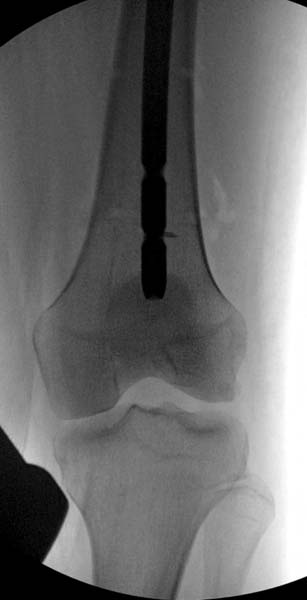

> Больная стабильная после хирургических мероприятии и получив добро,

> приступили к закрытому вправлению таранной кости с укладкой наружного

> фиксатора. Затем укладка больную на бок и открытый остеосинтез

> стабильная.. На третьий день провели стабилизацию перелома бедра

> антеградным остеосинтезом.